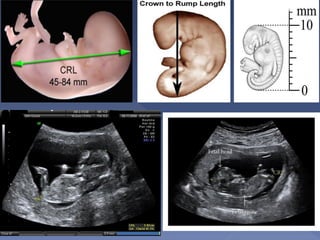

 Measure from top of head

to rump

 Always measure in neutral

position

 made between 7 to 13

weeks

 Very accurate(Dating

with the CRL can be

within 3-4 days of LMP)

 it should not be changed

by a subsequent scan.